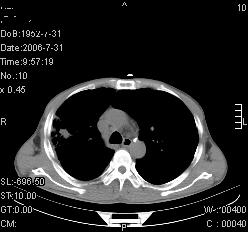

患者,男,54岁,咳嗦,咳痰20天。抗炎治疗2周。现esr76mm/h,目前患者症状明显好转,但发现两次ct片未见明显变化。两次分别做与7.25、7.31。第一次诊断右肺上叶炎症累计胸膜。大家看,从影像上内排除结核吗?

结核的可能性非常大,右上肺病变应该考虑干酪性肺炎。理由:

1.纵隔内多发淋巴结肿大。

2.esr76mm/h。

3.虽经抗炎治疗肺窗病灶有所吸收、减小,但纵隔窗病灶形态、密度、范围无明显变化。如果是单纯的大叶性肺炎,“抗炎治疗2周,目前患者症状明显好转”病灶应该基本消散了,至少也处于吸收消散期,密度变淡、范围变小。同时本病例所示其内的密度不均匀,见多发大小不一空洞样影也不符合大叶性肺炎吸收消散期表现。

病灶特点:片状 索条 结节混杂影,部分融合,密度不均,广泛累及相应胸膜.

临床治疗;二周未吸收.但症状好转.

多考虑:肺结核.